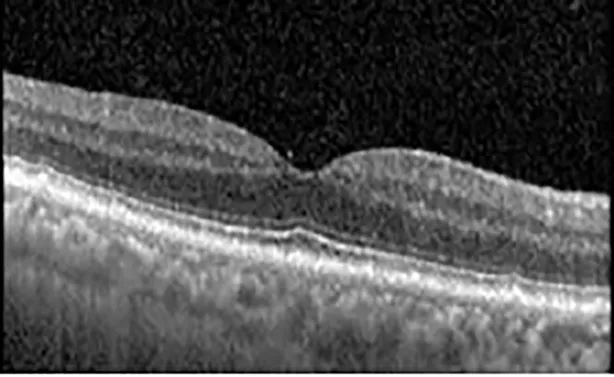

The patient began treatment with oral pemigatinib daily and was followed up for an ophthalmic examination during the second treatment cycle approximately 5 weeks into the treatment process. The patient had at this stage received 28 doses of 13.5 mg per day, which was administered in cycles of 14 on-days and 7 off-days, and had no visual or ophthalmic complaints. The non-corrected VA was OD 20/30 + 1 and OS 20/20. The OCT examinations revealed subfoveal SRF bilaterally. The fundus examination was otherwise unremarkable outside the patient’s prior documented peripheral drusen. Repeat autofluorescence was overall unchanged, though a slight hypofluorescent ring may be visualized in Figure 2. The current pemigatinib protocol recommendation for asymptomatic patients suggests no dose modification; however, with worsening presentation or positive symptoms, it is recommended to withhold pemigatinib. After discussion with the patient’s oncologist, it was decided to continue the medication at this time. Serial monitoring of the patient’s symptoms, vision, and SRF were conducted on specific days during active treatment cycles and days off-cycle to monitor the SRF. Subsequent evaluations demonstrated complete resolution of SRF while off-cycle, and asymptomatic re-accumulation of fluid while on-cycle with varying levels of VA. (Table 1) As we see demonstrated in the table below, in the later stages of the active cycles, such as day 13 of 14 of cycle 2, day 13 of 14 of cycle 3, day 13 of 14 of cycle 4, and day 14 of 14 on cycle 5, the patient’s VA showed no correlative changes based on the presence of SRF. The fluctuations in the patient’s VA certainly occurred, but were likely to be secondary to surface changes, as certain off-cycle days actually presented with lower acuities than days when the SRF was present on OCT examination.

Table 1

| Cycle, day, on/off | VA OD; OS | CMT OD; OS | OCT OD | OCT OS |

|---|---|---|---|---|

| Prior to initiation | 20/40; 20/20−2 | 274; 275 | ![]() | ![]() |

| Cycle 2, day 13/14, on | 20/30+1; 20/20 | 365; 355 | ![]() | ![]() |

| Cycle 2, day 4, off | 20/30−2; 20/20−2 | 282; 280 | ![]() | ![]() |

| Cycle 3, day 6/14, on | 20/40−1; 20/30−1 | 306; 301 | ![]() | ![]() |

| Cycle 3 day 13/14, Oon | 20/50+1; 20/30−2 | Poor tracing; 376 | ![]() | ![]() |

| Cycle 3, day 3, off | 20/30−1; 20/25 | 320; 329 | ![]() | ![]() |

| Cycle 3, day 10, off | 20/50−2; 20/30−1 | 269; 276 | ![]() | ![]() |

| Cycle 4, day 8/14, on | 20/50−2; 20/30 | 333; 317 | ![]() | ![]() |

| Cycle 4, day 13/14, on | 20/40−2; 20/25 | 360; 348 | ![]() | ![]() |

| Cycle 4, day 1, off (9/6) | 20/30; 20/25−1 | 273; 271 | ![]() | ![]() |

| Cycle 5, day 14/14, on | 20/30−1; 20/20 | 375; 364 | ![]() | ![]() |

| Cycle 5, day 6, off | 20/40+2; 20/30−2 | 276; 278 | ![]() | ![]() |

Highlights the visual acuity, central macular thickness, and the physical OCT of the macula for this patient in both the right and left eyes during various stages of the patient's chemotherapy treatment cycle.